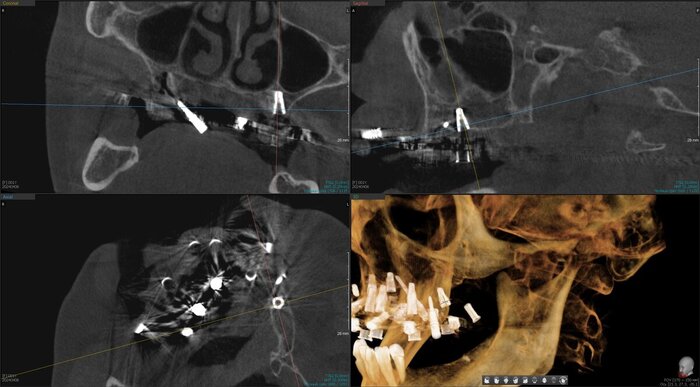

Получилось так, что сверху всего 8 зубов, по 4 с каждой стороны. Чёрная точка (которую вы точно увидите, скос эмали на зубе 1.1) - конструктивные особенности, всё это будет закрыто пломбировочным материалом. Зуб 1.1 - дополнительный имлантат, который потом планируем убрать. Он нужен лишь для усиления, ибо торк полноценный был получен только на одном из остальных 6-ти установленных.

Напоминаю - протезы временные адаптационные

Так же важный момент - верхний протез соприкасается с нижним только в точках полученного торка (их всего 2), остальное "на весу" и жевать не способно.

Рекомендации - мягкая, жидкая пища 4 месяца! Это важно.

Низ - всё ок.

не играет решающей роли ,сколько дней от имплантации до постановки протеза прошло. Важен торк (усилие) и пассивность конструкции. То есть протез на имплантаты должен усаживаться без боли, пассивно.

И будет успех.